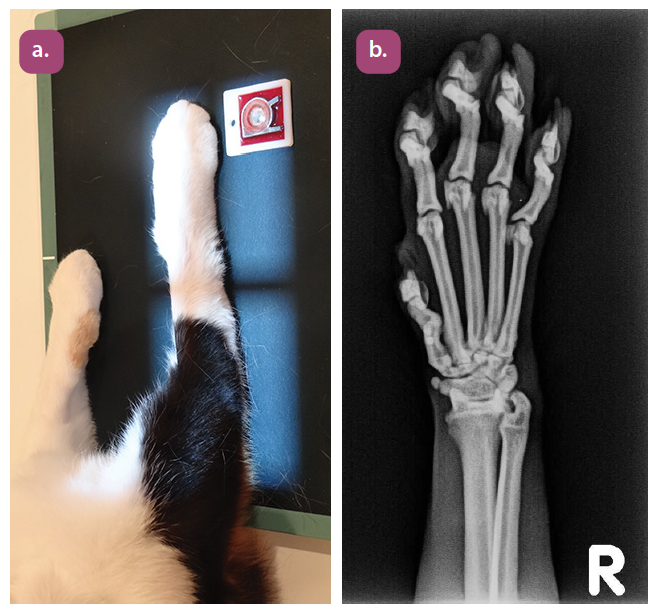

dorsopalmar projection of the metacarpus

mediolateral projection of the metacarpus

dorsopalmar projection of the phalanges

mediolateral projection of the phalanges